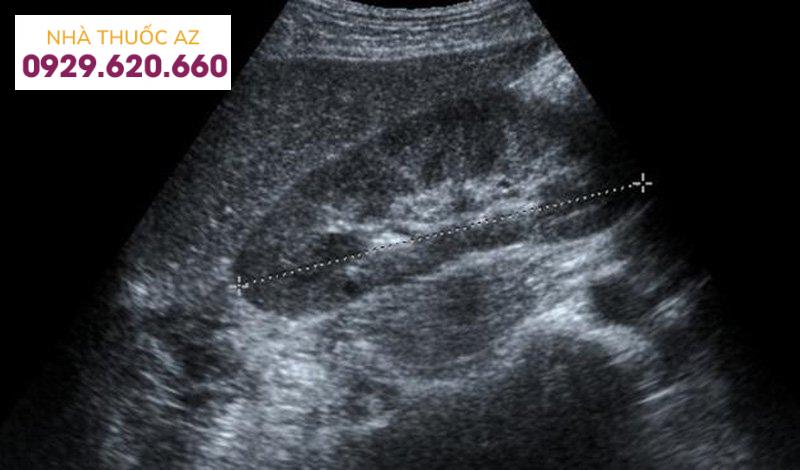

Chụp cắt lớp vi tính (CT): Thủ tục này kết hợp thiết bị X-quang đặc biệt với các máy tính tinh vi để tạo ra nhiều hình ảnh kỹ thuật số hoặc hình ảnh của gan. Bạn có thể được sử dụng thuốc nhuộm tương phản trước khi xét nghiệm để giúp bác sĩ nhìn rõ hình ảnh gan hơn. Xét nghiệm này giúp xác định mức độ nghiêm trọng của bệnh xơ gan cũng như các bệnh lý gan khác.Siêu âm gan: Siêu âm là một loại hình ảnh kiểm tra sử dụng sóng âm thanh để tạo ra hình ảnh bên trong bụng và / hoặc xương chậu, bao gồm cả hình ảnh của gan. Siêu âm Doppler cho phép đánh giá lưu lượng máu đến và từ gan.Elastography: Xét nghiệm này đánh giá độ cứng của gan và có thể giúp chẩn đoán mức độ nghiêm trọng của sẹo trong gan (được gọi là xơ hóa gan). Nếu không được điều trị, xơ hoá gan cuối cùng có thể dẫn đến xơ gan mà không thể tái tạo lại được. Elastography có thể phát hiện độ cứng của gan do xơ gan sớm hơn so với các xét nghiệm hình ảnh khác.Chụp cộng hưởng từ cơ thể (MRI): Xét nghiệm hình ảnh này sử dụng từ trường mạnh, xung tần số vô tuyến và máy tính để tạo ra hình ảnh chi tiết về gan cho phép đánh giá thiệt hại do các bệnh gan khác nhau gây ra. Với xét nghiệm này, bạn có thể được sử dụng thuốc tương phản từ để giúp bác sĩ nhìn rõ hình ảnh gan hơn.Chụp đường mật cộng hưởng từ (MRCP): MRCP là loại giao thức MRI đặc biệt được thiết kế để đánh giá một phần của gan và túi mật, được gọi là hệ thống mật là một phần của gan.Độ co giãn cộng hưởng từ (MRE). Xét nghiệm hình ảnh tiên tiến không xâm lấn này có chức năng phát hiện gan cứng hoặc chất dịch của gan bị cứng.Nội soi: sử dụng một ống linh hoạt gắn đầu chiếu sáng và máy ảnh. Nó có thể được sử dụng để tìm kiếm các mạch máu bất thường được gọi là giãn tĩnh mạch. Những hình ảnh này cho thấy sẹo xơ gan ngăn chặn lưu lượng máu trong tĩnh mạch cửa mang máu đến gan, hay theo thời gian, áp lực tích tụ trong tĩnh mạch này, hay tình trạng máu chảy ngược vào các mạch máu trong dạ dày, ruột hoặc thực quản.

Hình ảnh két quả siêu âm gan